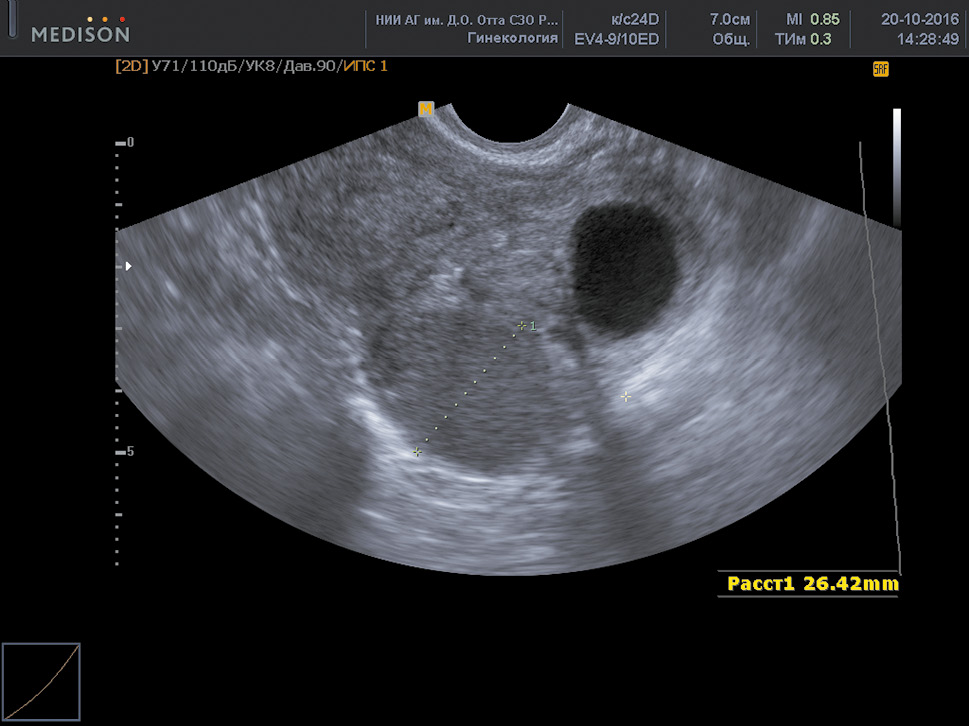

With nodular and focal forms of adenomyosis, the scans reveal the following echographic signs:

- Zones of increased echogenicity of a round or oval shape with smooth contours in the uterine wall with nodular endometriosis, and with uneven contours in case of focal endometriosis.

- Small (2–6 mm in diameter) anechoic inclusions or cystic cavities containing a finely dispersed suspension.

- Increased echogenicity near the proximal edge of the formation and reduced echogenicity near the distal front.

- Closely adjacent bands of medium and low echogenicity in the pathological focus, oriented perpendicular to the scanning plane.

- Deformity of the median uterine echo with the submucosal location of the nodule. The uterine thickness in focal and nodular adenomyosis depends on the size of the pathological formation (Fig. 4).

Fig. 4. Nodular adenomyosis

Рис. 4. Узловая форма аденомиоза